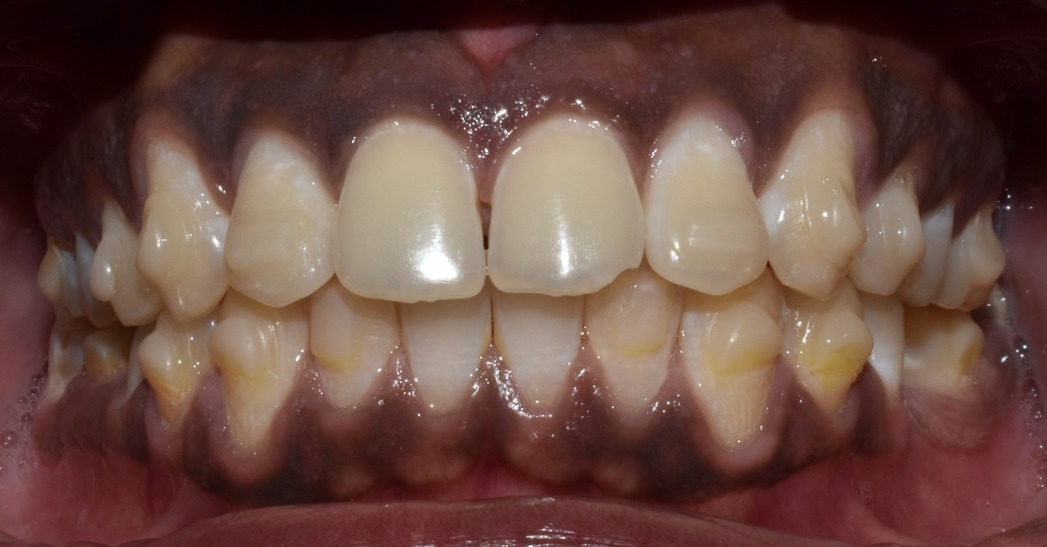

Before & After Results

At Aline Dent, we take pride in delivering visible and lasting improvements in our patients’ smiles. Our before-and-after results highlight the effectiveness of modern dental treatments combined with personalized care. This gallery showcases real dental cases treated at our clinic, giving you a clear idea of how different dental concerns can be corrected with the right treatment approach.

From minor corrections to complete smile enhancements, these teeth transformation results demonstrate how professional dental care can improve both oral health and appearance. Our experienced dental team carefully evaluates each patient’s needs and creates customized treatment plans to achieve natural, healthy, and confident smiles.

In this gallery, you will find a variety of smile makeover cases, including treatments for crooked teeth, gaps, discoloration, damaged teeth, and other common dental concerns.